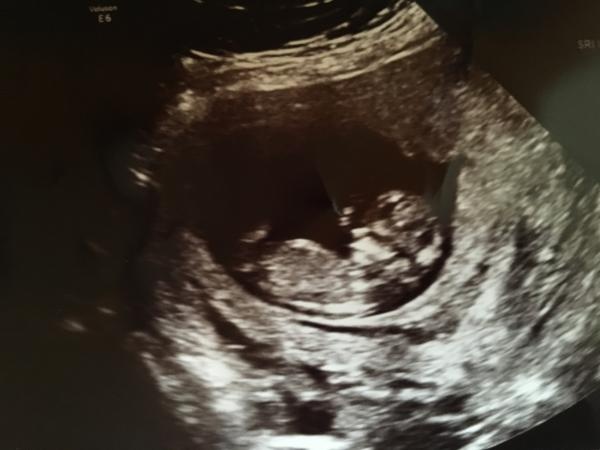

fen skrev 2017-02-23 08:00:49 följande:

Vecka 12 ????

Flicka?

dreamer74 skrev 2017-02-24 20:56:27 följande:

Ni som gissat flicka på min bild har gissat rätt enligt läkaren på dagens RUL.

Grattis :)